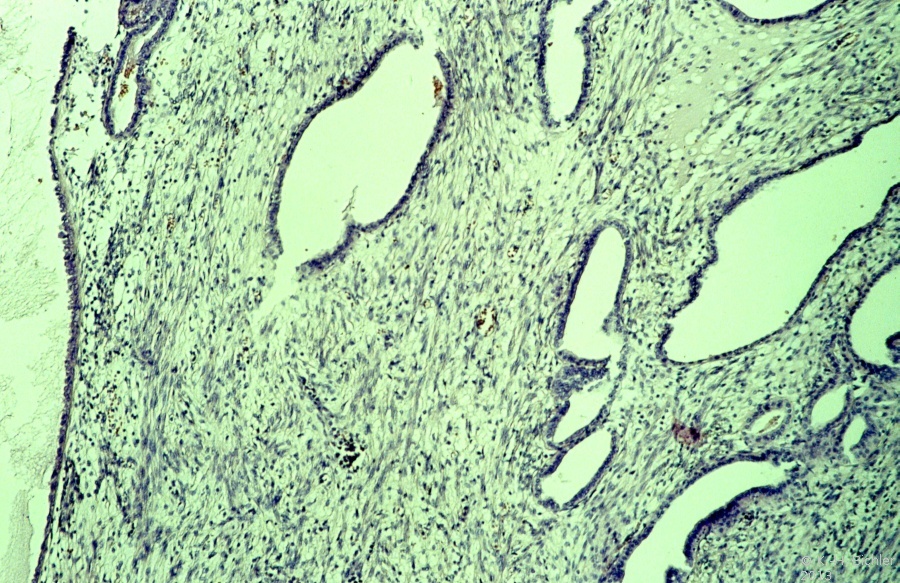

Mikroskopisch ist der Wilmstumor gekennzeichnet durch Gewebe, das verschiedenen Stufen der Nephrogenese entspricht. Es finden sich blastemische, stromale und epitheliale Zelltypen. Zum epithelialen Anteil gehören Strukturen, die tubulär oder glomerulär aufgebaut sind. Fibrozyten und myxoide Formen gehören zu den stromalen Gewebsarten. Auch glatte Muskelzellen, Knorpel-, Fett- und neurales Gewebe finden sich. Grundsätzlich ist festzuhalten, dass der Wilmstumor histologisch heterogen bzw. triphasisch aufgebaut ist. Die Anteile der Komponenten sind verschieden und korrelieren mit der Malignität des Tumors (Abbildung 2).

Tumoren des Stadium I (begrenzt auf die Niere) sind zumeist aus epithelialen Strukturen aufgebaut. Die vornehmlich aus blastomatösem Gewebe bestehenden Geschwülste gehören zu den Stadien III und IV (Stadieneinteilung s. später). Ungefähr 5% der Wilmstumoren enthalten anaplastische Nester. Die Zellen enthalten hyperchrome, große, pleomorphe (polymorphe) Kerne mit abnormalen Mitosen. Diese Tumoren sprechen im allgemeinen schlecht auf die Chemotherapie an und sind nicht komplett resezierbar (Abbildung 2).